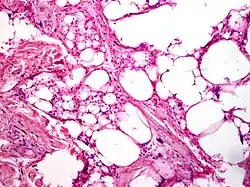

Stanowi 40–45% wszystkich przypadków tłuszczakomięsaka. Jest to guz lokalnie złośliwy, często wytwarzający liczne wznowy miejscowe[4], ale niemal nie daje przerzutów odległych, o ile nie ulegnie odróżnicowaniu[5]. Najczęstszymi lokalizacjami są kończyny (około 40%), tułów (30%) i przestrzeń pozaotrzewnowa (20%), rzadziej pojawia się w klatce piersiowej (5%) i okolicy głowy i szyi (3%)[6]. Makroskopowo jest to duży, dobrze odgraniczony guz o guzkowej powierzchni. Zwykle jest to pojedynczy guz, choć w przestrzeni pozaotrzewnowej może być to kilka guzów. Przybiera kolor od żółtego do białego w zależności od udziału w nim adipocytów, zwłóknienia i obszarów śluzowatych. W dużych guzach mogą występować obszary martwicy tłuszczowej. Mikroskopowo dojrzały tłuszczakomięsak składa się z dojrzałych proliferujących adipocytów ze znacznym zróżnicowaniem wielkości komórek. Ogniskowo jest widoczna atypia jądrowa z nadbarwliwymi (hiperchromatycznymi) jądrami. Komórki te mają tendencję do gromadzenia się w pobliżu przegród łącznotkankowych. Również komórki zrębowe są nadbarwliwe i wielojądrowe. Wiele lipoblastów zawiera pojedyncze lub liczne wakuole w cytoplazmie[7].